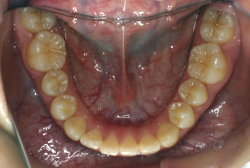

成長発育期の叢生症例・非抜歯治療

今回は「歯並びの凸凹を治したい」という主訴で来院したケースです。診断の結果、「成長発育期の叢生」と判明しました。叢生とは歯並びの凸凹のことですが、この方の場合は上顎が少々重症で、上の犬歯が外側へ飛び出し、いわゆる「八重歯」という状態でした。凸凹の解消のためには永久歯を抜歯して隙間を作って残った歯をきれいに配列する方法(抜歯法)と、歯列を拡大して配列する方法(非抜歯法)の2種類があります。歯列の拡大にはさらに2つの方法が有り、横方向へ拡大する場合と、臼歯を後方に移動させて拡大する方法があります。今回の症例のようなケースでは、横方向へ拡大してもあまり効果的ではなく、後方への移動が最適です。上の臼歯を後方へ移動させるために、今回はヘッドギヤという取り外し式の装置を、夜寝る時に半年ほど使用していただきました。

注意点としてここでお伝えしたいのは、矯正専門医ではない歯科医院で、いわゆる「床矯正」という方法を行うと、たいてい横方向の拡大になってしまいます。無駄に横方向の拡大をするとかえって症状を悪化させたり、何の効果もないことになってしまいます。一見簡単そうな矯正に見えたとしても、しかるべき矯正専門医に診断してもらうことをおすすめします。

この方の場合、治療期間はヘッドギアを6ヶ月、マルチブラケット法を7ヶ月でした。治療後は凸凹が改善しただけでなく唇の審美性が大幅に改善しました。もちろん噛み合わせ的にも正しい状態が確立しています。